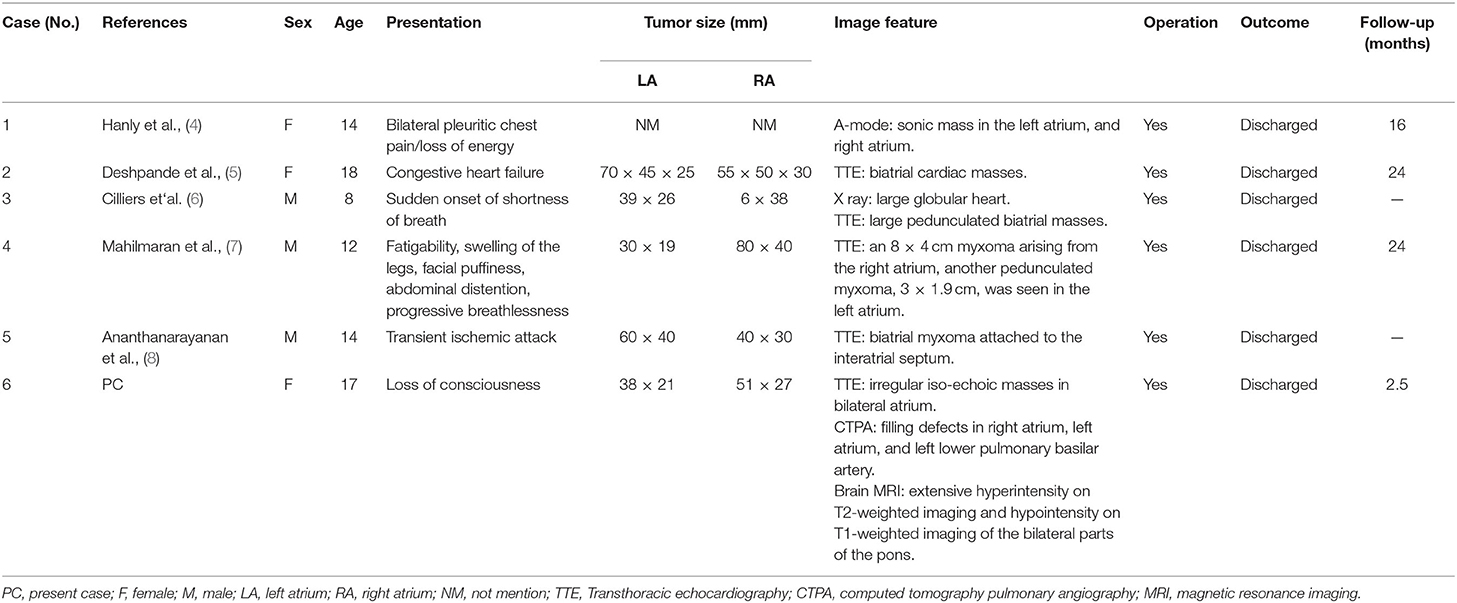

In order to present the literature review, case reports of all biatrial myxoma among child and adolescent patients in the English language were searched from the PubMed, Web of Science, and Ovid databases, dating between January 1, 1980 and August 31, 2021. Key words were used for the search, which included “biatrial myxoma,” “bilateral atrial myxoma,” “bilateral Atrial myxomas,” “pulmonary embolism,” and “cerebral embolism.” The flow chart of the literature screening process is presented in Figure 5. A total of five articles involving five cases were included in the analysis. For each case, we documented the first author, publication year, and the patient's age, sex, presentation, tumor size, image features, operation, outcome, and follow-up results (Table 1).

Table 1. The cases of biatrial. myxoma in children and adolescent patients from the literature review.

According to the literature, from January 1980 to August 2021, only 44 cases of biatrial myxoma have been reported. Our results revealed a predominance of biatrial myxoma between 40 and 65 years of age (52.2% of the cases), however, only six cases have been reported for patients of 18 years or less (about 13.6%; including of our case) of biatrial myxoma, comprising three girls and three boys, with a female to male ratio of 1:1. Remarkably, the presentation of these patients was predominantly associated with embolic events, such as pulmonary embolism and cerebral embolism. However, all patients with pulmonary and cerebral embolism had only one or the other, and the occurrence of both pulmonary and cerebral embolism simultaneously has not been reported. Fortunately, most patients were discharged after surgical operations, suggesting that biatrial myxoma has a relatively good prognosis.